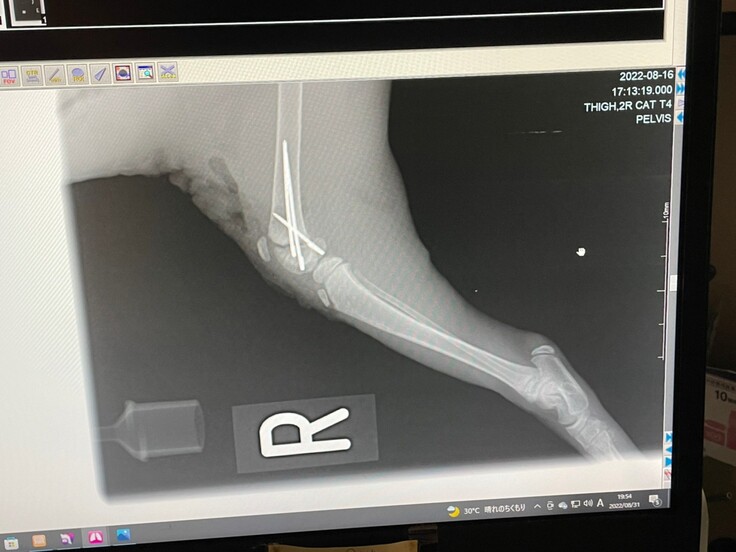

新着情報にも記載させていただきましたが、がおは1月19日に再手術が決まりました。

生後1か月ほどで手術を行ったため、脚を固定するボルトがうまく刺さっておらず、歩く邪魔になっており、撤去することになりました。